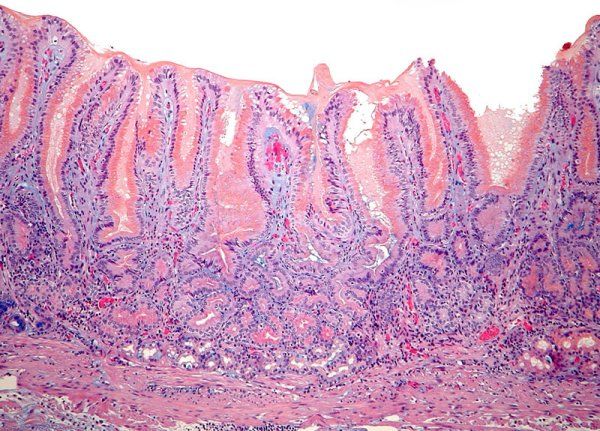

1. Superficial

1. Invasiva local

1. Tejidos profundos